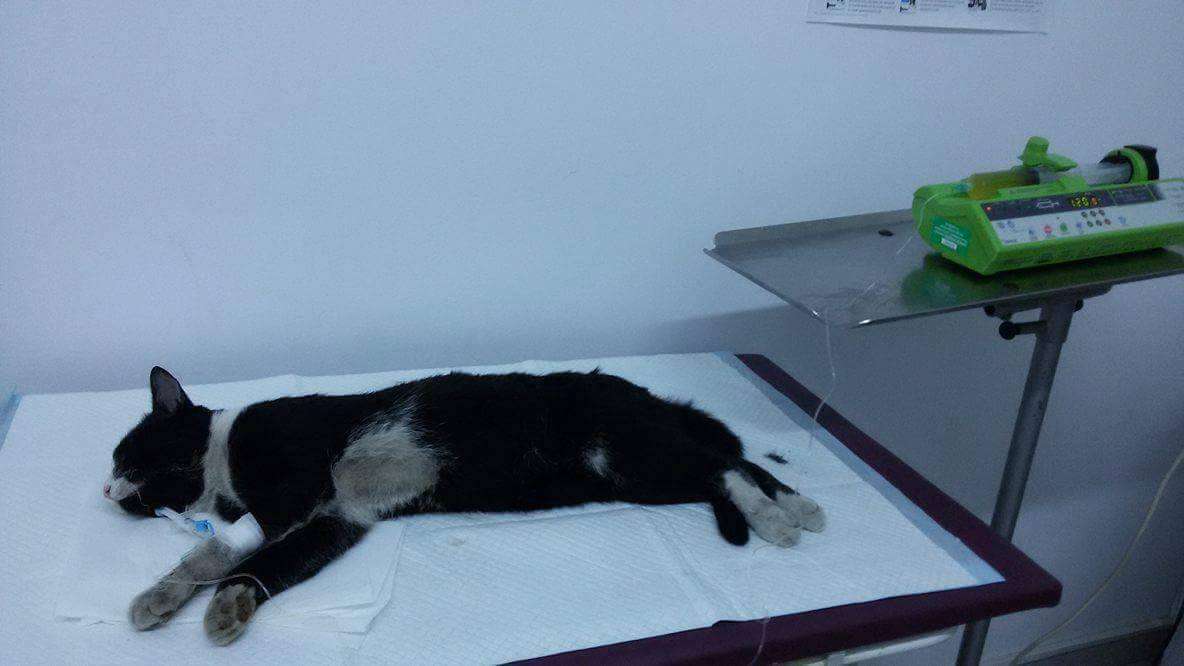

This is how a brute with a human face wanted to kil her female dog. Because the dog got pregnant, she threw her on the street but, because the dog did not move from the front side of the house no matter how many times she sent her away, she decided to kill the dog in a very brutal way. She put more than 100 pins in food and the poor starved soul swallowed everything without even breathing. The female dog underwent three surgeries and we hope she won’t have permanent negative effects because of these injuries caused by needles. When she gets well and gets out of the hospital, the sanctuary APAM will be her home. I want you to know that this brute will not remain unpunished and we took all the necessary steps for this to happen. Now she has a criminal record and we won’t give up until she receives the heaviest punishment. Please join us and help us cover all medical costs and substantial expenses in our trial in court against this cruel brute . Thank you!

UPDATE:The sweet little one, is feeling really bad

R.I.P. tormented soul :(( …we hoped until the last second that day will come in which we`ll keep you in our arms and to offer you a wonderful life.BUT our battle with the monster who has killed you, CONTINUES!